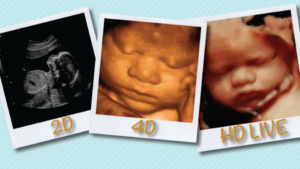

Many of the other benefits of ultrasound are either unnecessary (e.g., getting a picture of their face), possible to determine with other methods (e.g., their age, if there are twins, or if they have a genetic defect), or possible to determine around the time of labor (e.g., if a C-section is necessary).